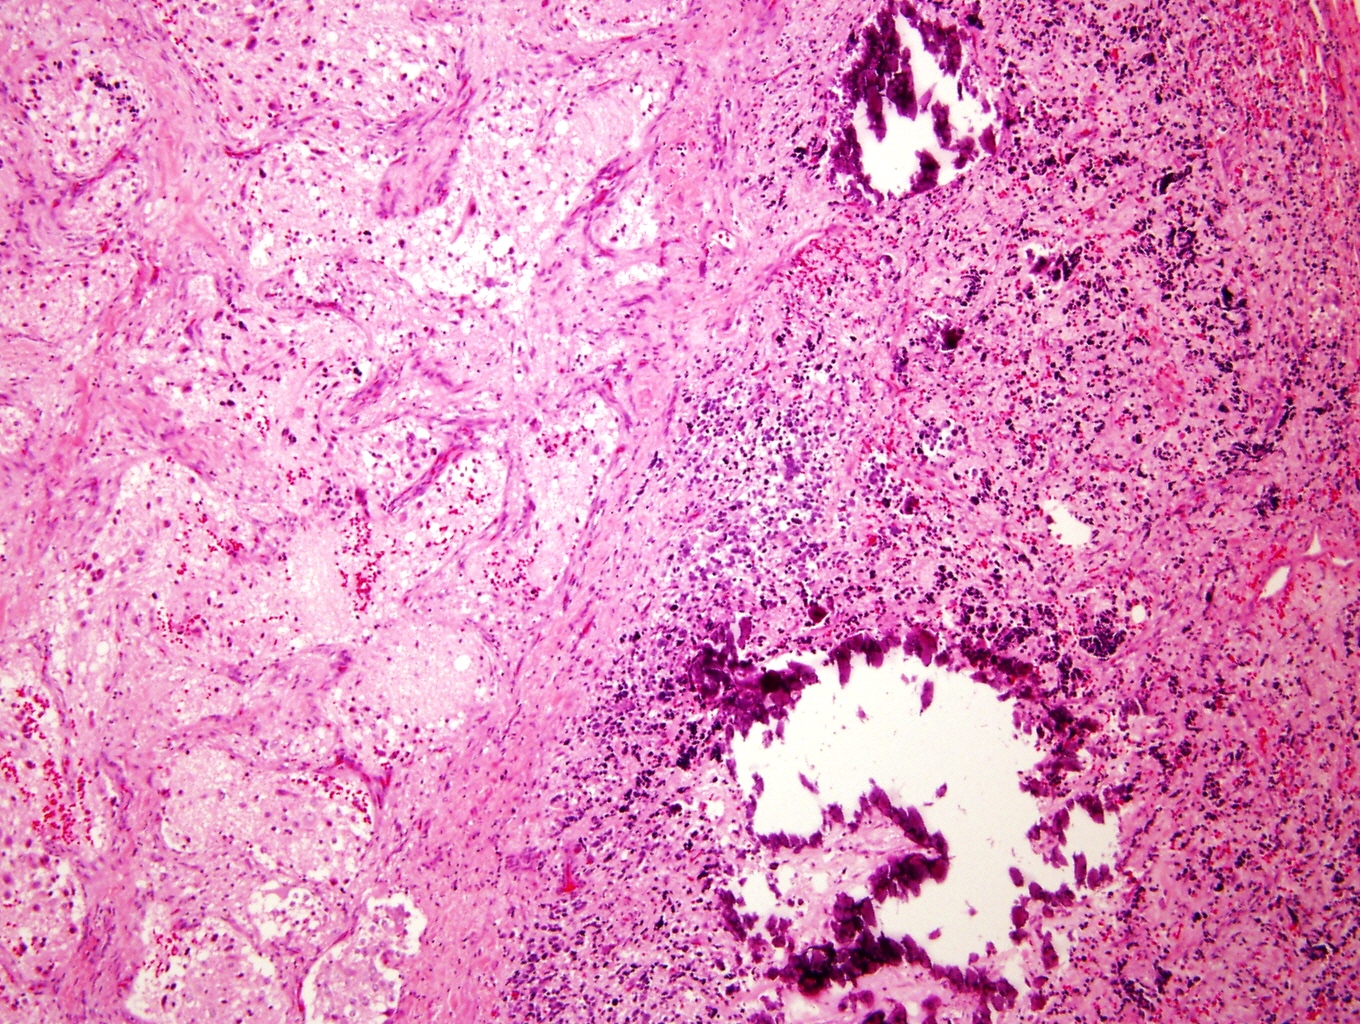

Microscopic (histologic) description

- Architecture: lobular, diffuse / solid, organoid

- Neuroblasts

- Homer Wright pseudorosettes = circular, ovoid, angular zones of pale staining neuritic cell processes surrounded by tumor cell nuclei; may rarely palisade

- Minimal cytoplasm, may have cytoplasmic tail

- Round to ovoid nuclei with stippled salt and pepper chromatin, inconspicuous nucleoli

- Ganglion cells

- Abundant granular eosinophilic cytoplasm (Nissl substance = rough endoplasmic reticulum)

- Distinct cell borders

- Nuclear enlargement, eccentric nuclei, prominent nucleoli

- May see neuromelanin pigment (brown, finely granular; rarely present), cystic degeneration, hemorrhage, dystrophic calcification